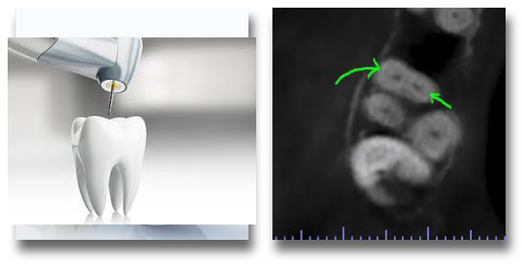

Endodontics

• Early detection of periapical disease

• 3D imaging of root canal system, leaving no scope for missed canals

• Endodontic surgical planning

• Evaluation of Dentoalveolar trauma

• Evaluation of vertical root fractures, separated instruments, and retreatment cases

• Determining outcome of treatment